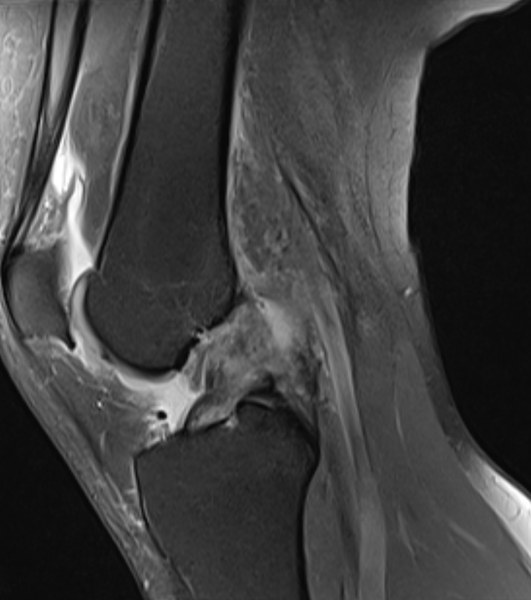

I’m injured. Again. This time it’s bad. An ordinary posthole on a scramble resulted in seven separate tears in my knee.

This injury would be plain bad luck if it wasn’t one of a series. In the last three years, I’ve broken my foot and torn the cartilage in my elbow. How did I get here?

IMG_0042.JPEGThe MRI revealing tears in Lauren's knee. Photo courtesy of Lauren Allen.